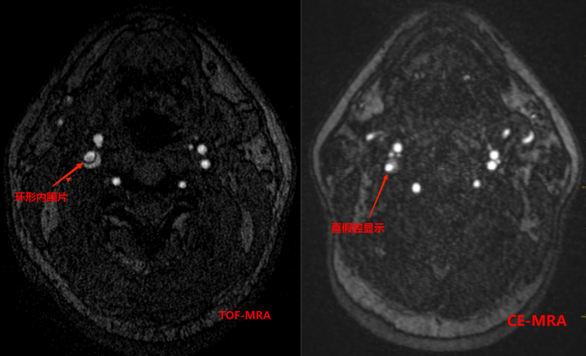

3招丨找出壁间血肿(动脉夹层)

ef67d9fa36dc94c9d4ac5fd611a15201.png

1 TOF-MRA图可见颈内动脉内膜片影

2 CE-MRA图可见颈内动脉真假腔显示

266bdc3b78e99e1e45b42d871817ee31.png

13D-T1-SPC图显示打药前颈内动脉C1C2段高亮的壁间血肿及管腔重度狭窄。

23D-T1-SPC图显示打药后血肿及相应节段血管壁都强化不明显。